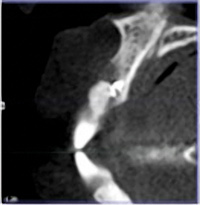

A 33-year-old woman presented with a buccal fistula at the apex of No. 8, and there was an 8-mm mid-buccal probing depth (Figure 1). The tooth had been treated multiple times by an endodontist. Based on the tooth's dental history, mobility, and its poor endodontic and periodontal prognosis, it was deemed hopeless and scheduled for extraction (Figure 2).

The patient returned at 4 months postoperatively for site evaluation (Figure 11). Bone sounding with an anesthetic needle indicated formation of hard bony surface. At 4 months lamellar bone is present.7 A cone-beam computed tomography (CBCT) scan of site No. 8 radiographically confirmed that the bony ridge had been regenerated (Figure 12). CBCT measurements indicated the maxillary ridge was 6.44 mm wide and 21 mm tall.

Fig 2. Preoperative CBCT confirmed absence of buccal bone.

Figure 2

Fig 12. CBCT at 4 months postoperative showed vertical bone regeneration.

Figure 12